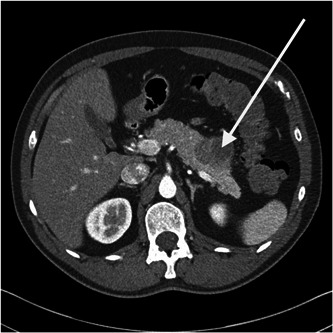

Other imaging (ultrasonography, X‐ray, computerized tomography [CT], and/or magnetic resonance imaging; Figure 1) was performed in 74.5% of the patients. Nearly 85% of the patients with an unknown tumor location underwent one of the latter. Almost three quarter of the patients with gastric NET did not receive any kind of imaging and diagnosis was mainly based on endoscopy. No relationship between diagnostic imaging and overall survival (p = 0.067), neither progression free survival (p = 0.32) could be observed Supporting Information: Table 9A,B).

Figure 1.

Computed tomography of the abdomen (arterial phase) showing a pancreatic neuroendocrine tumor (arrow).